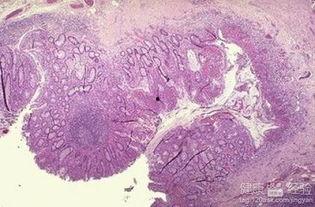

结肠炎,顾名思义,就是结肠发炎了。它是一种常见的肠道疾病,主要症状包括腹泻、腹痛、便秘等。结肠炎的类型有很多,比如溃疡性结肠炎、克罗恩病等,每种类型都有其独特的症状和治疗方法。